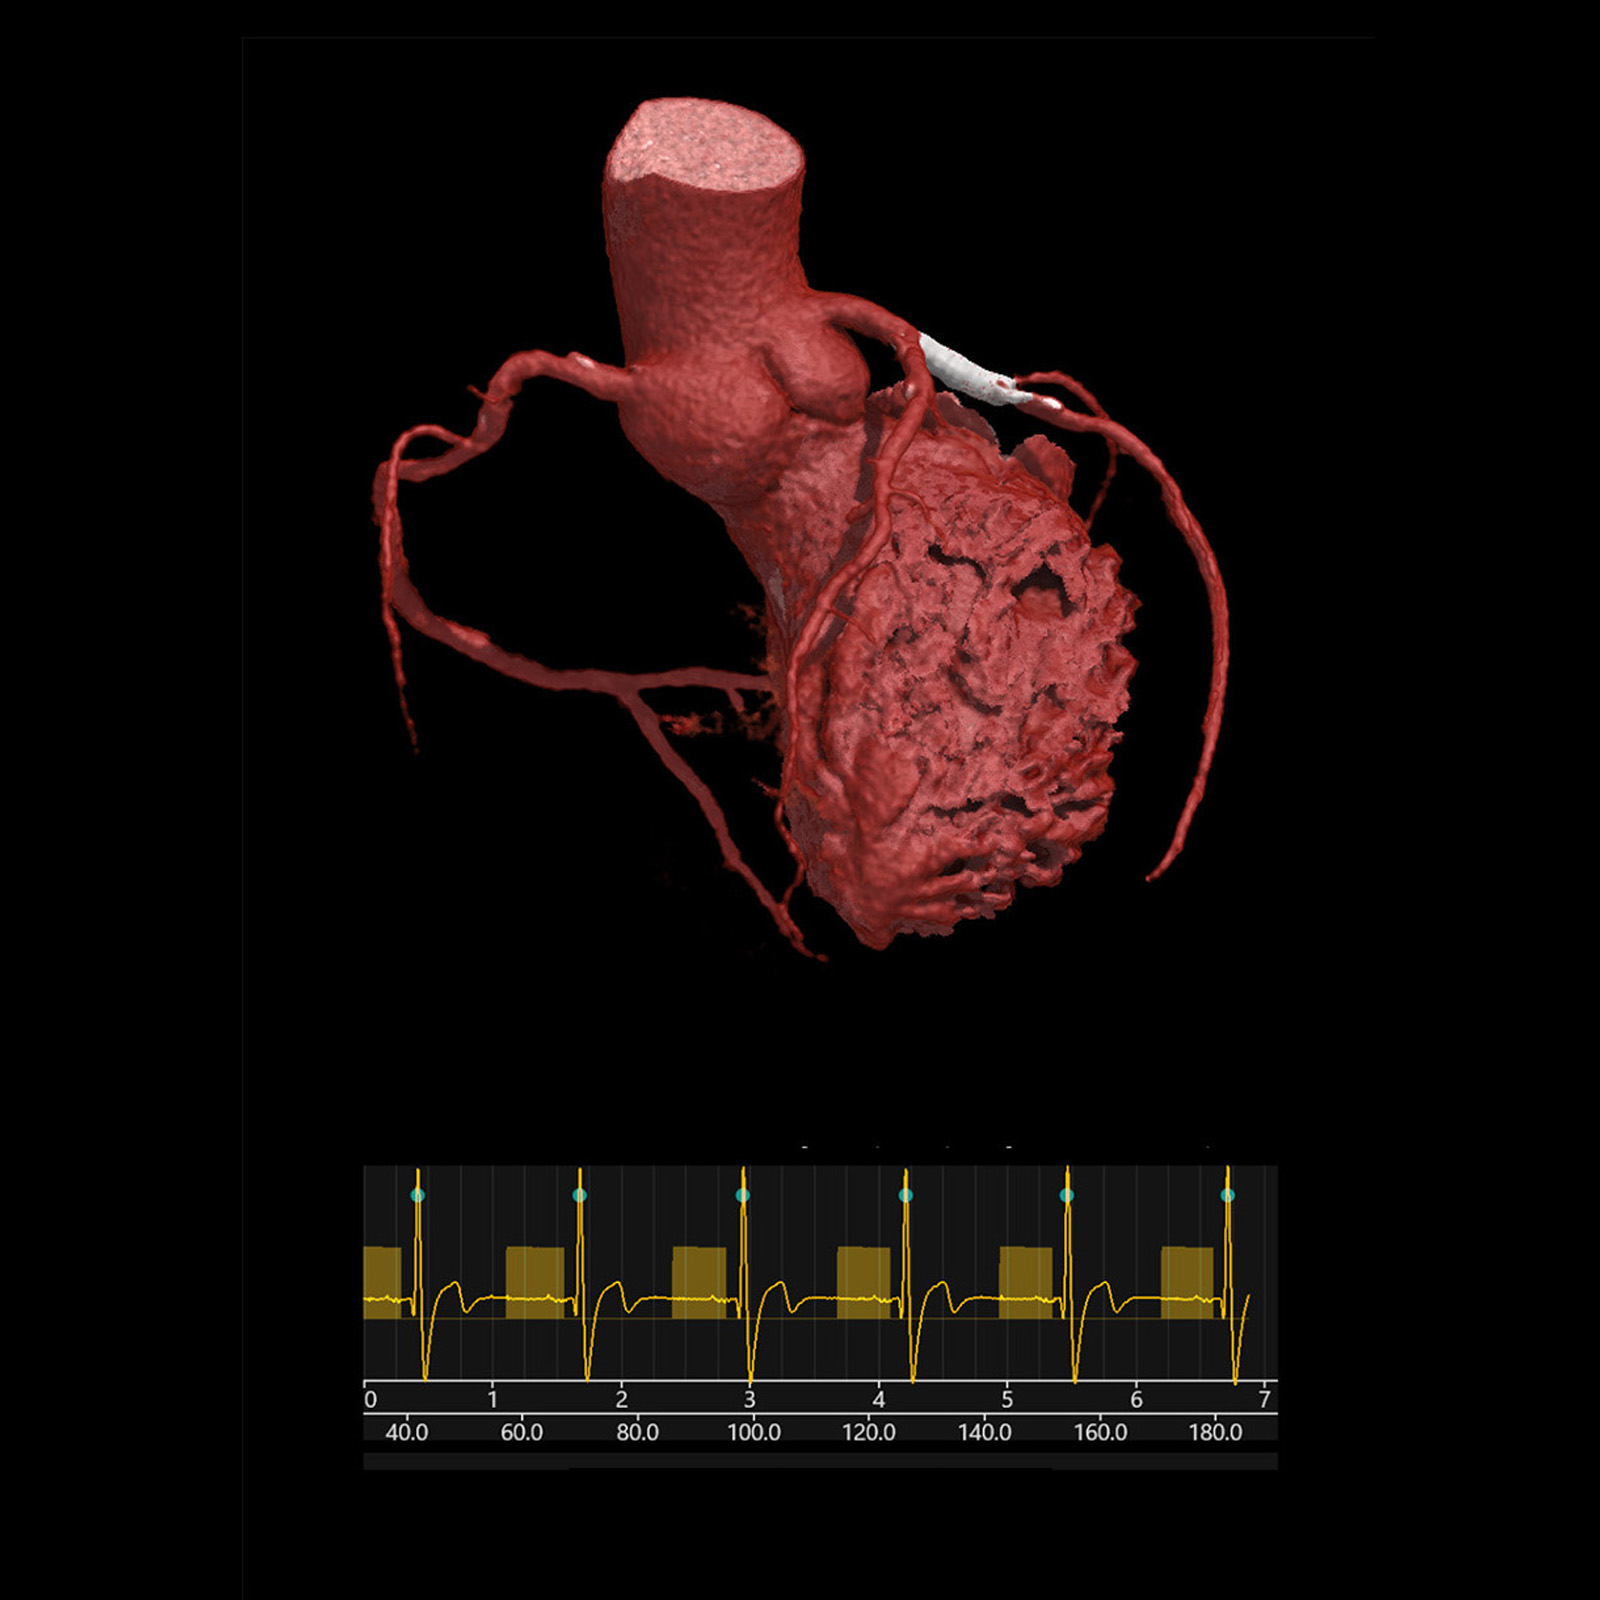

Low Dose Cardiac, 1.8 mSv

Aquilion Serve SP

Excellent temporal resolution at a low dose for this prospectively gated heart scanned on the Aquilion Serve SP with SURECardio* suite of Cardiac CT workflow automation tools and AI-trained image quality from Advanced intelligent Clear-IQ Engine (AiCE) Deep Learning Reconstruction, providing high quality and low noise images.

View Scan Parameters

View Scan Parameters

| Scan Mode | kVp | mAs | Reconstruction | CTDIvol | DLP | Effective Dose† |

|---|---|---|---|---|---|---|

| Helical | 120 | SUREExposure 3D | AiCE DLR | Cardiac | 7.5 mGy | 112.2 mGy·cm | 1.8 mSv |

† AAPM Report 96, k-factor 0.014

* Option

Courtesy Sunshine Coast Radiology, Australia